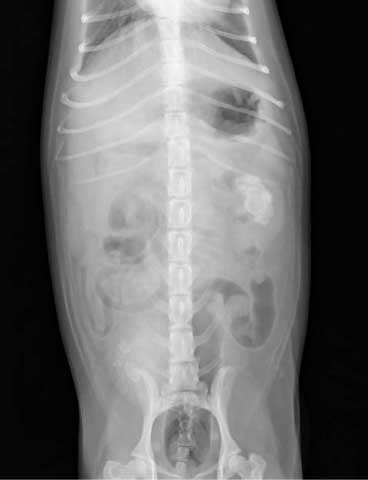

レントゲン検査

腎臓の大きさ、形態や結石を確認することができます。また、必要に応じて造影剤を使用することでさらに腎臓の詳細な評価が可能です。

造影方法は静脈性と逆行性の2種類があります。静脈性尿路造影は、静脈から造影剤を投与して造影剤の尿中への排泄を経時的に確認する方法で、腎臓や尿管の構造の評価や尿生成過程から腎機能の評価を行うことが可能です。逆行性尿路造影は、ペニスや膣など陰部から造影剤を投与する方法で、奇形や腫瘤といった形態上の異常や膀胱から尿道にかけての尿路の狭窄や断裂・破裂の有無を評価することが可能です。

単純レントゲン/ 膀胱結石および左腎結石を認める